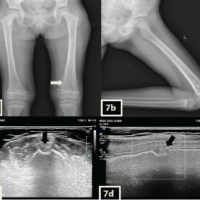

A 16-year-old female presented to orthopedics OPD in Government Stanley Medical College and Hospital with complaints of progressive swelling over the left elbow region for the past 5 years associated with pain over the elbow joint. The patient was examined and on palpation, a non-tender, hard mass was located over the anterolateral aspect of the elbow. It was non-reducible, non-compressible, and fixed to the underlying bone. Terminal flexion and rotational movements of the elbow were restricted. On investigation, a plain X-ray of the elbow showed exostosis in the proximal radius metaphysis. CT and MRI were taken, which showed a 3 × 4 × 2.4 cm size swelling arising from the proximal metaphyseal region of the radius with a cartilaginous cap of 2.4 mm (Fig. 2).

An 18-year-old male presented to the outpatient department in Government Stanley Medical College Hospital with complaints of progressive swelling over the left iliac region for the past 5 years associated with pain while sitting and sleeping in a decubitus position. The patient was examined. On palpation, a tender hard mass was located poster superior to the left anterior superior iliac spine (ASIS) of the iliac bone. The skin over the swelling was free and mobile. On investigation, a plain X-ray pelvis showed exostosis in the iliac bone. MRI was taken and it showed a swelling of size 8.1 × 5.3 × 6.1 cm present in the left iliac bone with irregular cartilaginous cap thus confirming our diagnosis (Fig. 3).